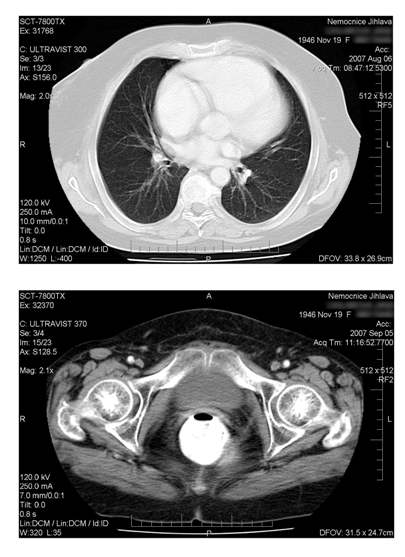

Histologicky šlo o epidermoidní karcinom. V dubnu 2007 vysloveno na

vaginálním UZV podezření na lokální recidivu. V květnu 2007

potvrzena lokální recidiva v pánvi a navíc zjištěny mnohočetné

metastázy do plic.

Pacientka zahájila chemoterapii režimem CDDP +

topotecan v dávkování CDDP 50 mg/m2 1.den a topotecan

0,75 mg/m2 1.-3.den s intervalem 3 týdnů. Po. 4.cyklu v

srpnu 2007 byla provedena kontrolní CT vyšetření a bylo zjištěno

úplné vymizení všech metastáz na plicích. Podobně vymizel i

patologický nález v malé pánvi. Po podání 5 cyklu byla léčba

ukončena.